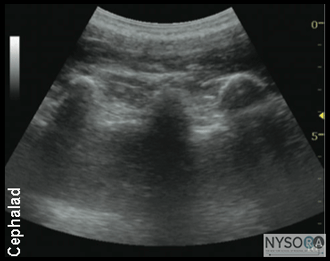

Figure 1: Transducer position (curved transducer, longitudinal view) to image the central neuroaxis, transverse processes, and estimate the needle and depth to the lumbar plexus using a longitudinal view. Anatomy and Sonoanatomy Lumbar plexus block, also known as psoas compartment block, comprises an injection of local anesthetic in the fascial plane within the posterior aspect of the psoas major muscle. Because the roots of the lumbar plexus are located in this plane, an injection of a sufficient volume of local anesthetic in the postero-medial compartment of the psoas muscle results in block of the majority of the plexus (femoral nerve, lateral femoral cutaneous nerve, and the obturator nerve). The anterior boundary of the fascial plane that contains the lumbar plexus is formed by the fascia between the anterior two thirds of the compartment of the psoas muscle that originates from the anterolateral aspect of the vertebral body and the posterior one third of the muscle that originates from the anterior aspect of the transverse processes. This arrangement explains why the transverse processes are closely related to the plexus and therefore are used as the main landmark during LPB.

Longitudinal Scan Anatomy ![]() Figure 4: Patient position (lateral decubitus position) transducer (curved, linear array) placement and the needle insertion angle to block the lumbar plexus using oblique transverse view. Regardless of the technique, the operator first should identify the transverse processes on a longitudinal sonogram (Figure 1). One technique is to first identify the flat surface of the sacrum and then scan proximally until the intervertebral space between L5 and S1 is recognized as an interruption of the sacral line continuity. Once the operator identifies the transverse process of L5, the transverse process of the other lumbar vertebrae are easily identified by a dynamic cephalad scan in ascending order. The acoustic shadow of the transverse process has a characteristic appearance, often referred to as a "trident sign" (Figure 2A). Once the transverse processes are recognized, the psoas muscle is imaged through the acoustic window of the transverse processes. The psoas muscle appears as a combination of longitudinal hyperechoic striations within a typical hypoechoic muscle appearance just deep to the transverse processes (Figure 2B). Although some of the hyperechoic striations may appear particularly intense and mislead the operator to interpret them as roots of lumbar plexus, the identification of the roots in a longitudinal scan is not reliable without nerve stimulation. This unreliability is partly due to the fact that intramuscular connective tissue (e.g., septa, tendons) within the psoas muscle are thick and may be indistinguishable from the nerve roots at such a deep location. As the transducer is moved progressively cephalad, the lower pole of the kidney often comes into view as low as L2-L4 in some patients (Figure 3A and B). Transverse Scan Anatomy ![]() A Kirchmair and colleagues were among the first to describe the sonoanatomy of relevance for LPB. (3) They reported the ability to accurately guide a needle to the posterior part of the psoas muscle, where the roots of the lumbar plexus are located, using ultrasound guidance in cadavers. (4,5) Since, significant advances in ultrasound technology have taken place, allowing for much improved image quality, which have allowed Karmakar and colleagues to devise an alternative approach to the lumbar plexus using ultrasonographic identification of the transverse processes as the guide. (6) With this scanning technique, the transducer is positioned 4 to 5 cm lateral to the lumbar spinous process at the L3-L4 level and directed slightly medially to assume a transverse oblique orientation (Figure 4). This approach allows imaging of the lumbar paravertebral region with the erector spinae muscle, transverse process, the psoas major muscle, quadrates lumborum, and the anterolateral surface of the vertebral body (Figure 5A, B, and C). In the transverse oblique view, the inferior vena cava (IVC), on the right-sided scan, or the aorta, on the left-sided scan, also can be seen and provide additional information on the location of the psoas muscle, which is positioned superficial to these vessels. In this view, the psoas muscle appears slightly hypoechoic with multiple hyperechogenic striations within. The lower pole of the kidney can often be seen, when scanning at the L2-L4 level, as an oval structure that ascends and descends with respirations (Figure 6). The key to obtaining adequate images of the psoas muscle and lumbar plexus with the transverse oblique scan is to insonate between two adjacent transverse processes. This scanning method avoids acoustic shadow of the transverse processes, which obscures the underlying psoas muscle and the intervertebral foramen (angle between the transverse process and vertebral body) and allows visualization of the articular process of the facet joint (APFJ) as well. Because the intervertebral foramen is located at the angle between the APFJ and vertebral body, lumbar nerve roots often can be depicted.

More recently, Karmakar and colleagues described the "trident sign technique," which uses an easily recognizable ultrasonographic landmark, transverse processes, and an out-of-plane needle insertion. The trident sign technique derives its name from the characteristic ultrasonographic appearance of the transverse processes (trident) to estimate the depth and location of the lumbar plexus. After application of ultrasound gel to the skin over the lumbar paravertebral region, the ultrasound transducer is positioned approximately 3 to 4 cm lateral and parallel to the lumbar spine to produce a longitudinal scan of the lumbar paravertebral region (Figure 7). Then the transducer is moved caudally, while still maintaining the same orientation, until the sacrum and the L5 transverse process become visible (Figure 8). The lumbar transverse processes are identified by their hyperechoic reflections and acoustic shadowing beneath which is typical of bone. Once the L5 transverse process is visible, the transducer is moved cephalad gradually, to identify the L3-L4 level. The goal of the technique is to guide the needle through the acoustic window between the transverse processes (between the "teeth of the trident") of L3-L4 or L2-L3 into the posterior part of the psoas major muscle containing the roots of the lumbar plexus (Figure 2B). After obtaining ipsilateral quadriceps muscle contractions, the block is carried out using the previously described injection and pharmacology considerations (Figures 9 and 10). ![]() Figure 10: Local anesthetic (LA) disposition during injection of local anesthetic into the psoas muscle and the L2-L3 level. The spread of LA is often not well seen using two-dimensional imaging. LP, lumbar plexus; TP, transverse process. A paramedial scan also can be used with an in-plane needle approach. In this technique, an insulated needle is inserted in-plane from the caudal end (Figure 4) of the transducer while maintaining the view of the transverse processes. Again, the goal is to pass the needle and inject local anesthetic with a real-time visualization of the needle path and injection into the posterior part of the psoas muscle (Figure 5). In summary, ultrasound-guided LPB is a technically advanced procedure. Experience with ultrasound anatomy and less technically challenging nerve regional anesthesia techniques are useful to ensure success and safety. Although the use of ultrasound in LPB is not widely accepted, in expert hands, ultrasound guidance can increase the accuracy and possibly safety, by providing information on the location, arrangement, and depth of the osseous and muscular tissues of importance in LPB. It should be kept in mind that the dorsal branch of the lumbar artery is closely related to the trans-verse processes and the posterior part of the psoas muscle. Considering the rich vascularity of the lumbar paravertebral area, the use of smaller gauge needles and avoidance of this block in patients on anticoagulants is prudent. Injections into this area should be carried out without excessive force because high-injection pressure can lead to unwanted epidural spread and/or rapid intravascular injection. (7) Lumbar plexus block in patients with obesity or advanced age can be more challenging. Aging is associated with a reduction in skeletal muscle mass (sarcopenia) and replacement of the muscle mass by adipose tissue, leading to changes in ultrasound absorption and scattering. ![]() |